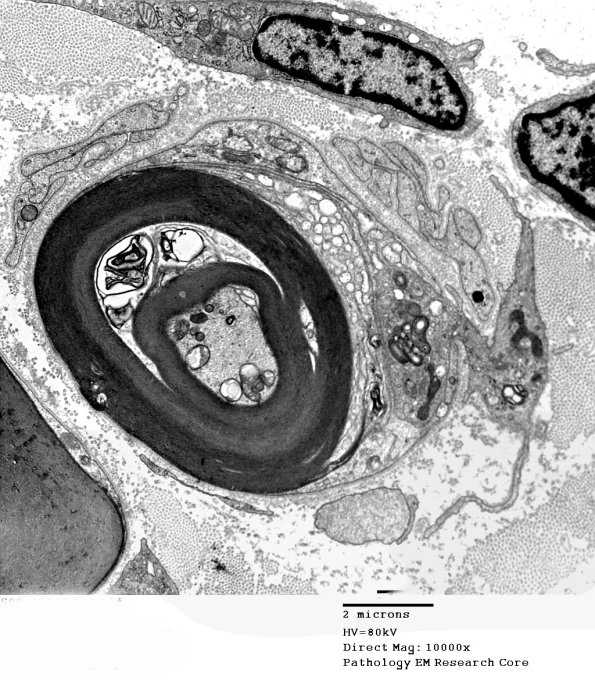

1D3A,B Another image of a macrophage displacing the Schwann cell sheath and basement membrane and beginning to engulf ultrastructurally normal myelin in the presence of an intact axon. (electron micrographs)